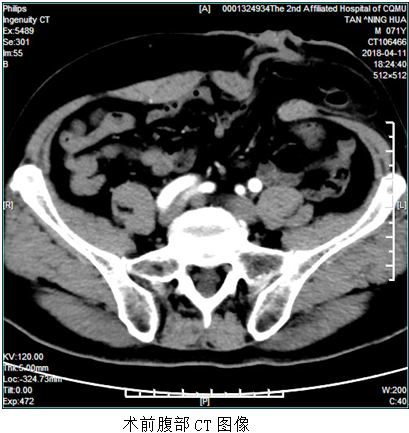

日前,重庆医科大学附属第二医院血管疝腹壁外科成功为一名结肠造口旁疝的患者实施了全腹腔镜下造口旁疝补片修补术,该术式为我院首例。患者